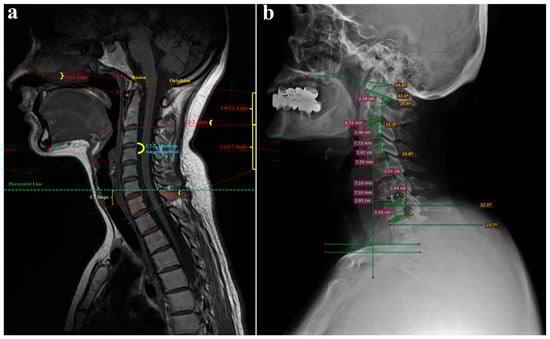

2.2. Radiological Assessment

2.5. Clinical and Radiological Assessment